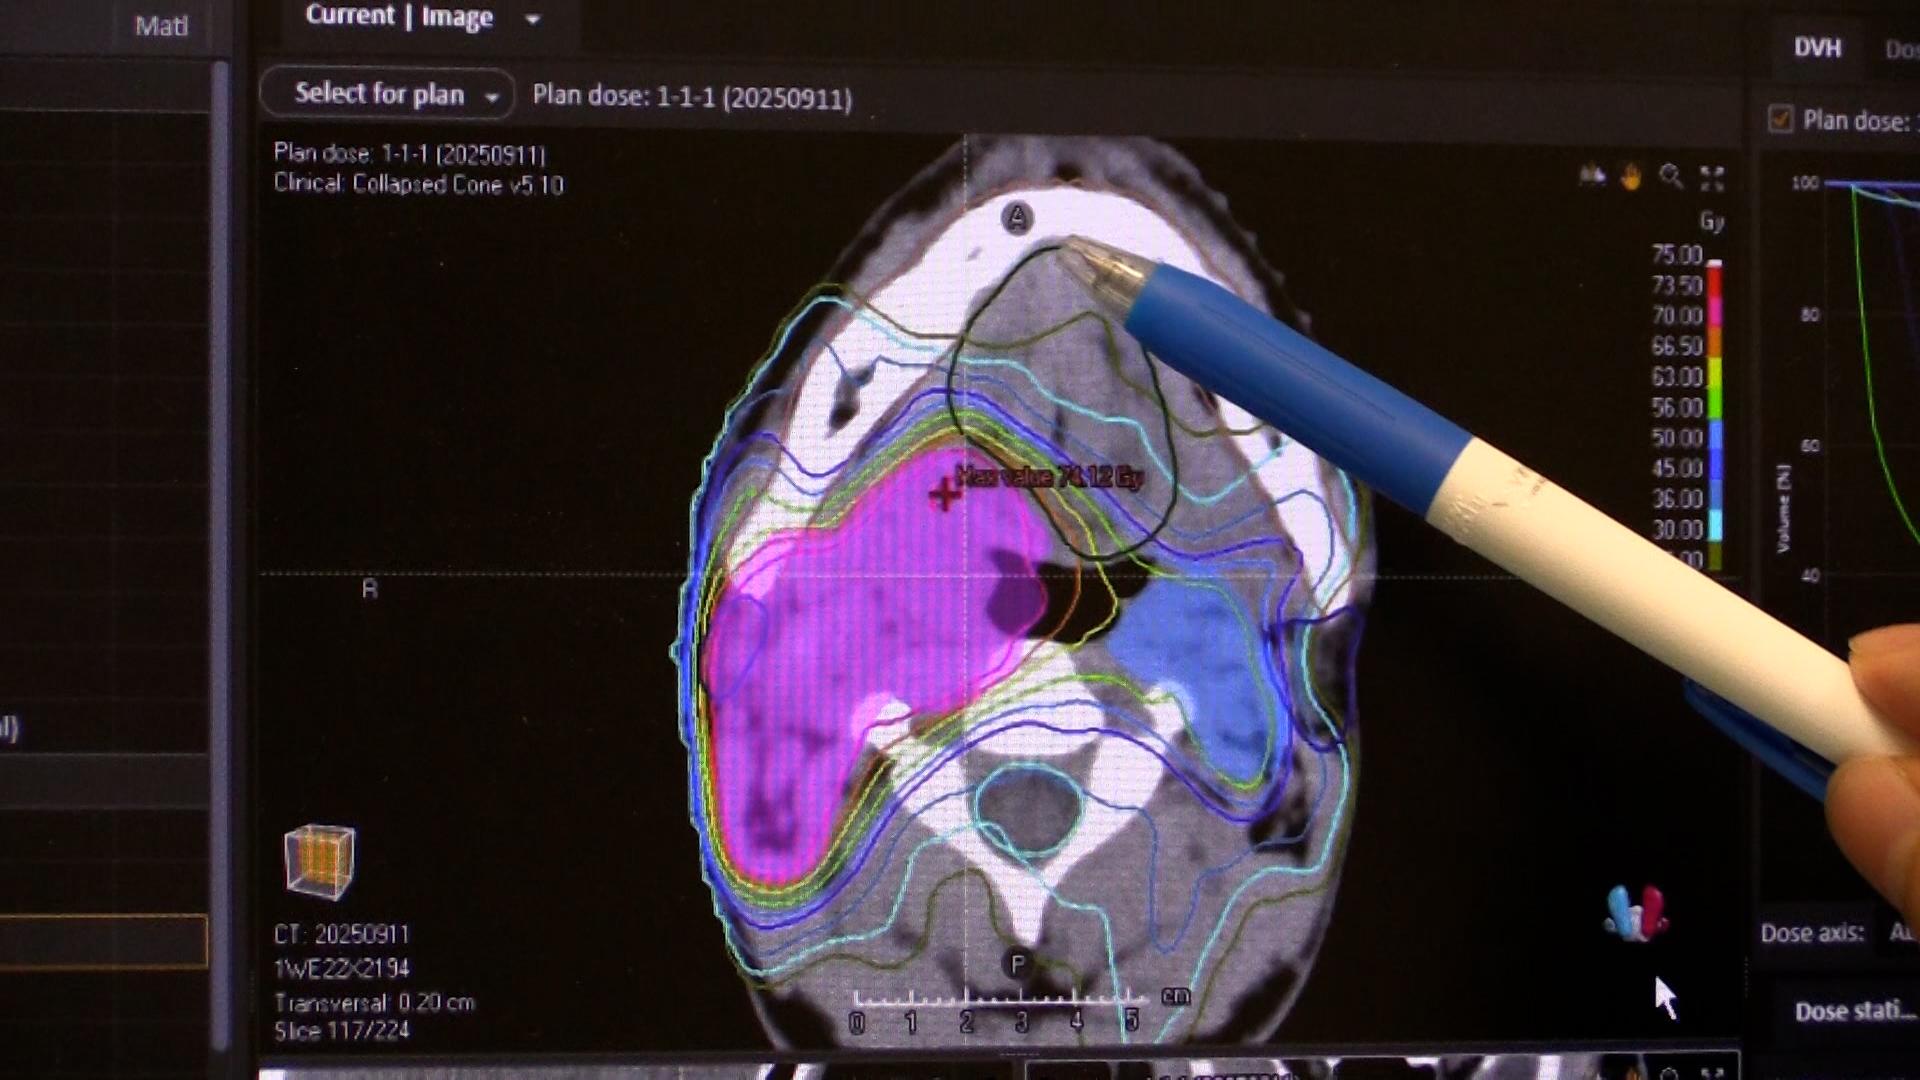

2人に1人が、癌になる時代。外科手術や薬物療法と並ぶ“癌治療の3本柱”の1つが、放射線治療だ。進化する癌の高精度放射線治療の最前線を取材。

2人に1人が、癌になる時代。外科手術や薬物療法と並ぶ“癌治療の3本柱”の1つが、放射線治療だ。「切らずに治せる治療」として身体への負担も少なく、仕事がある“現役世代”の患者が働きながら治療を受けられるメリットがあり、国内で新たに放射線治療を受ける癌患者は年間約23万人に増加している。

その放射線治療は、AIの進化などによる技術革新で、今後さらに治療の精度が上がることが期待されている。しかし、国内メーカーは装置の製造から相次ぎ撤退し、医療現場では海外メーカー製がシェアをほぼ独占する状態になっていた。ガイアは、進化する癌の高精度放射線治療の最前線を取材。これまでにない最新鋭の性能を武器に“悲願の国産装置”を開発した「日立ハイテク」と医師たちの挑戦を追う。